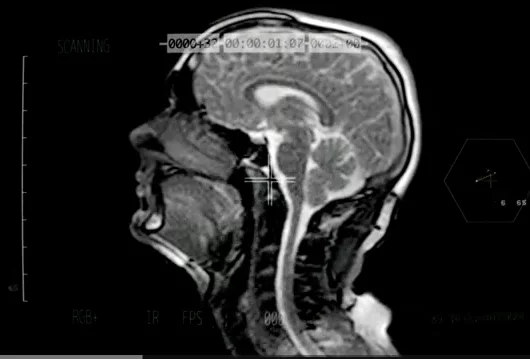

Przedmurze (łac. claustrum) to warstewka istoty szarej mózgu o grubości ok. 2 mm. Jest kluczowa dla powstawania świadomości. Najwyraźniej to przedmurze integruje wiele czynników świadomości w jedną, doświadczaną przez człowieka całość

Zaczęło się, gdy Koubeissi zamiast prądu o niskiej częstotliwości skierował głęboko w czaszkę pacjentki prąd o częstotliwości wysokiej. Gdy tylko pobudził prądem część mózgu zwaną przedmurzem, pacjentka straciła świadomość. A gdy prąd został wyłączony – natychmiast ją odzyskała. Ten zabieg powtarzano wielokrotnie w ciągu kilku dni – z identycznym skutkiem. Za każdym razem pacjentka pod wpływem prądu traciła świadomość, choć nie traciła przytomności. Jej wzrok gasł, przestawała reagować na głos i obecność lekarzy, a oddech ulegał spowolnieniu. Po przebudzeniu w ogóle nie pamiętała, co się stało. Odkryty sterownik świadomości działał jak prawdziwy pstryczek. To pierwszy przypadek w historii, gdy badaczom udało się sterować pojawianiem się świadomości poprzez elektrostymulację pojedynczego obszaru mózgu. Choć od ponad stu lat naukowcy przykładają do głowy badanych elektrostymulatory, osłabiając lub wyłączając różne obszary mózgu, to dotychczas nikt nie był w stanie wyłączyć świadomości. Teraz badacze planują powtórzenie eksperymentu na większej liczbie osób.

Choć wcześniejsze wyniki badań sugerowały, że przedmurze jest powiązane ze świadomością, mózgowy włącznik został poruszony dopiero teraz. Dr Koubeissi porównał cały proces do uruchamiania samochodu. – Auto potrzebuje wielu rzeczy, aby ruszyć: paliwa, silnika, skrzyni biegów – tłumaczy. – Ale jest tylko jeden moment, w którym wszystko razem zaczyna wspólnie działać – przekręcenie klucza w stacyjce. Chociaż świadomość to skomplikowany proces, być może właśnie odnaleźliśmy ten klucz.